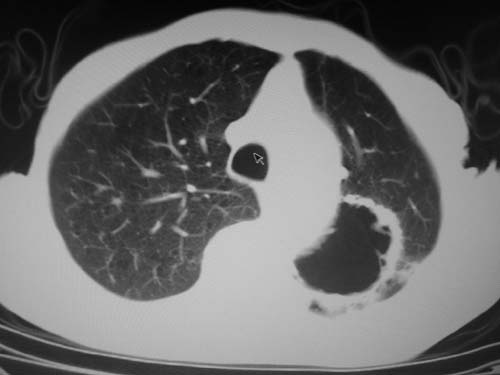

标题: CT19736:男,76岁,咳嗽,胸痛 [打印本页]

标题: CT19736:男,76岁,咳嗽,胸痛

支持左上肺周围型肺癌性并空洞形成伴胸椎转移。

左上沟癌空洞形成并胸椎转移。

考虑癌性空洞并胸椎转移。

空洞内壁有多发结节,支持癌性空洞。